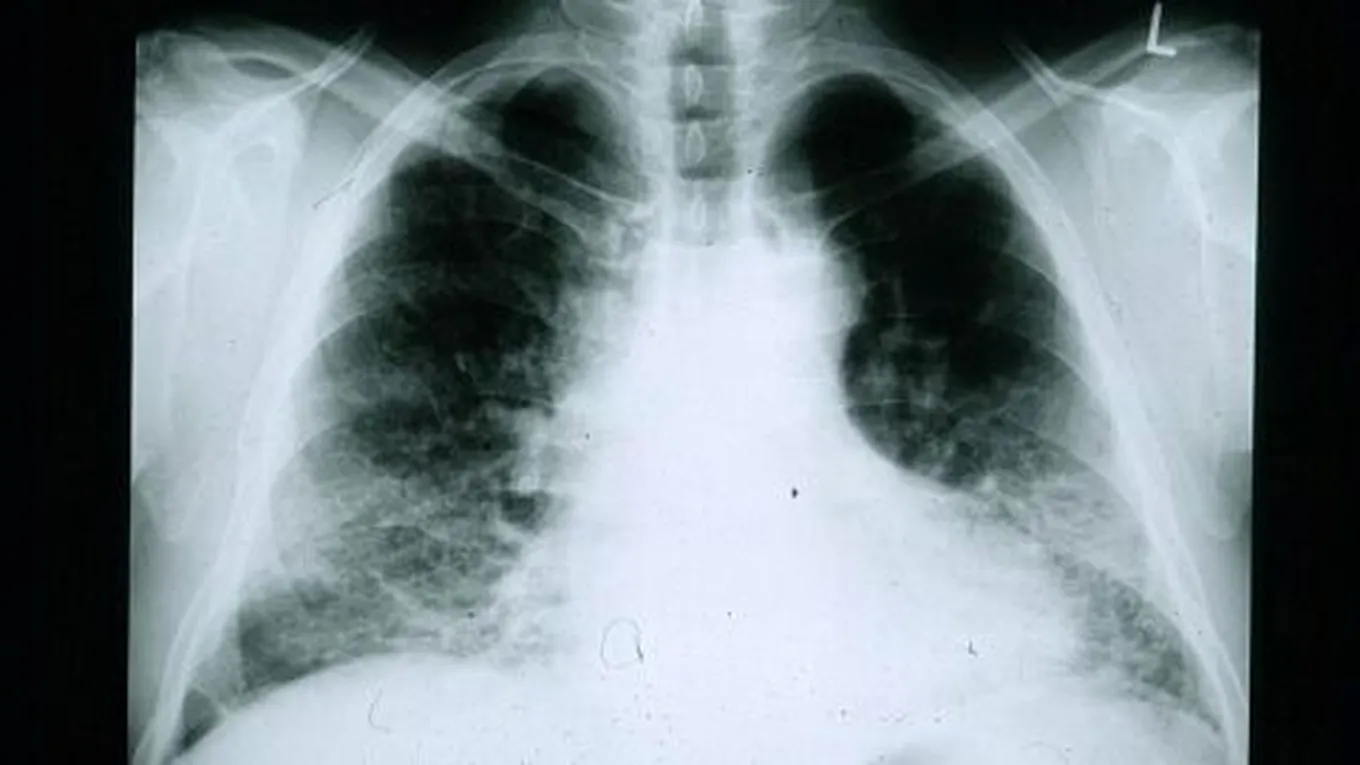

أسباب تليف الرئةيحدث تليف الرئة (بالإنجليزية: Pulmonary fibrosis) عند تلف نسيج الرئة وتندبه، إذ يصبح سميكاً ومُتيبساً مما يجعل أداء الرئة لعملها بشكلٍ صحيح

يحدث تليف الرئة (بالإنجليزية: Pulmonary fibrosis) عند تلف نسيج الرئة وتندبه، إذ يصبح سميكاً ومُتيبساً مما يجعل أداء الرئة لعملها بشكلٍ صحيح أكثر صعوبة، وبالرغم من عدم قدرة الأطباء على تحديد سبب حدوث المشكلة بدقة، إلا أنّ هناك مجموعة من العوامل التي تسبب تلف نسيج الرئة، ومنها ما يأتي:[1]